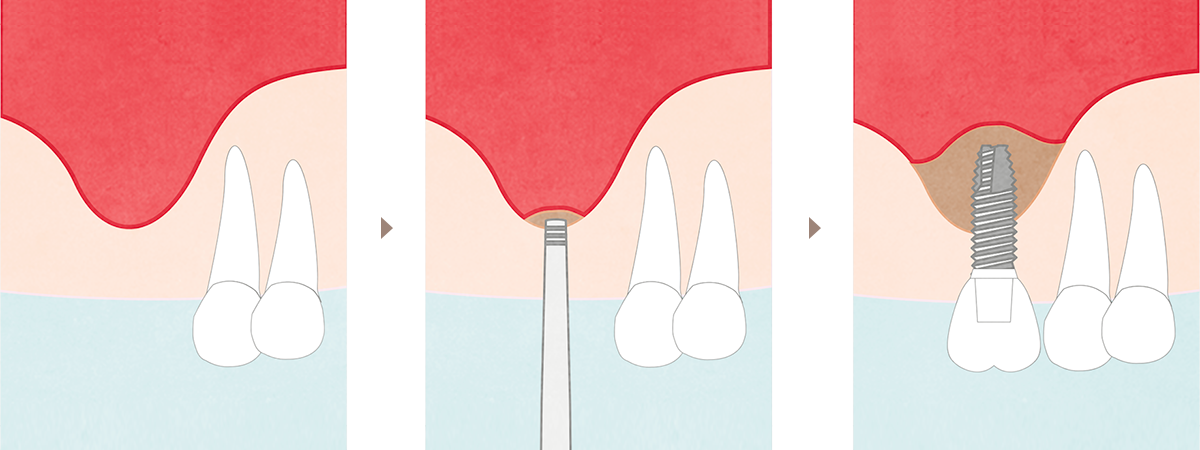

STEP.4 一次手術(インプラント埋入手術)

- インプラントを顎骨の中に埋め込みます。

(所要時間:30分~1時間程度/本)

STEP.5 二次手術(頭出し手術) ※ほとんどのケースでは必要ありません。

- インプラントと骨が結合してから、頭出し手術を行います。

歯肉を切開する必要がありますが、痛みに配慮しながら治療を行います。

骨が柔らかい場合と骨量が不足している場合は、二次手術が必要となります。

(所要時間:30分~1時間程度)